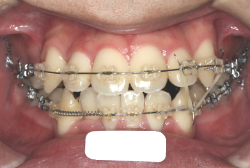

「前歯が重ならない」という主訴で来院したケースです。診断の結果、「重症の開咬」と判明しました。

この方の場合は、マルチブラケット装置は、歯の位置づけを3次元的に正確に行うことの出来る最善の矯正方法です。したがって開咬の治療も、形の改善としては問題なく行うことが出来ます。しかし、開咬が他の症状と少し違う点は、舌や唇の動かし方に問題があることから生じた症状なので、この問題を放置したまま形だけを作っても、時間が経つと簡単に後戻りしてしまうという問題です。つまり、マルチブラケット法で形態の矯正をするのと同時に、原因となっている筋肉の動きを正常に修正しなければなりません。この筋肉の動きを正常に修正する治療が、"筋機能訓練療法(Myo-functional therapy:略してMFT)"といわれるものです。

筋機能訓練療法は、筋機能訓練療法士という特別なトレーニングを積んだ歯科衛生士が行います。内容的には、いろいろなメニューがあり、簡単なものから始めて少しずつ筋肉の力を強めていき最終的には、無意識に起きる舌の突出をなくし、正しい摂食嚥下運動を獲得するまでトレーニングしていきます。この症例は、もちろん筋機能訓練にもしっかり取り組みました。治療後は開咬が改善しただけでなく、出っ歯の症状もなくなり唇の審美性が大幅に改善しました。もちろん奥歯の噛み合わせも正しい状態が確立しています。